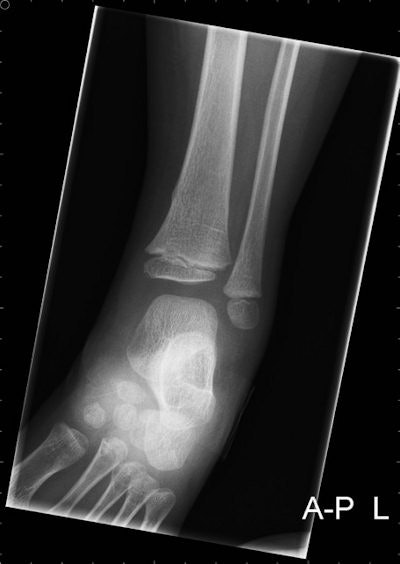

Radiographs of a 4-year-old boy with bicycle spoke wheel injury. Images courtesy of Annelie Slaar.Key study findings

In almost two-thirds of the patients (63%), radiography of two or more anatomical regions was performed. In 98 children (99%), the fracture was located at the distal tibia or fibula. All fractures were diagnosed on a radiograph of the ankle or lower leg (including the ankle region). No fractures of the foot were diagnosed.

There were 158 (49.4%) male patients with a mean age of 4.2 years (SD, 1.8). A total of 99 patients had a fracture, of which 48 patients were male. The peak incidence of both a bicycle spoke injury and a fracture was at 4 years of age. In all patients with a fracture, in whom a radiograph of the ankle and the lower leg was obtained, the fracture was visible on both the radiograph of the ankle and the lower leg.